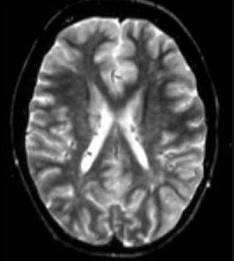

问题 根据MRI表现考虑为 ( )

选项 A、先天性脑积水 B、肝豆状核变性 C、脑面血管瘤病 D、神经纤维瘤病 E、结节性硬化症 一、单项选择题

答案 E